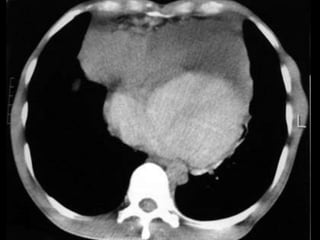

NO SEMINOMATOSOS

• Ubicación: mediastino anterior

• Edad: 30 años

• Clínica: por efecto de masa y secreción neurohumoral

• Variedades: coriocarcinoma, tumor del saco vitelino,

carcinoma embrionario y tumores mixtos

• Diagnóstico:

• TAC: masas necrosadas con hemorragias, de bordes mal

definidos, voluminosas

• PAAF

• GCH aumentada

• Alfafetoproteína aumentada

• CEA aumentado

• Tratamiento: QTX, en rescate Cirugía + RTX

NO SEMINOMATOSOS • Ubicación:mediastino anterior • Edad: 30 años • Clínica: por efecto de masa y secreción neurohumoral • Variedades: coriocarcinoma, tumor del saco vitelino, carcinoma embrionario y tumores mixtos • Diagnóstico: • TAC: masas necrosadas con hemorragias, de bordes mal definidos, voluminosas • PAAF • GCH aumentada • Alfafetoproteína aumentada • CEA aumentado • Tratamiento: QTX, en rescate Cirugía + RTX